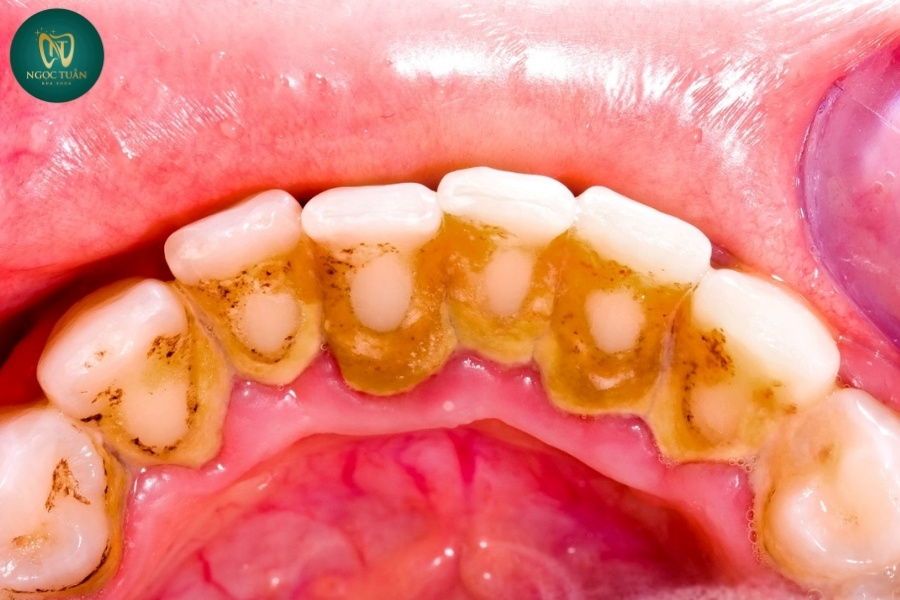

Vôi răng (cao răng) là những mảng bám chứa vi khuẩn, thức ăn thừa và khoáng chất từ nước bọt tích tụ trên bề mặt răng, đặc biệt là ở vùng viền nướu và kẽ răng. Khi không được làm sạch thường xuyên, những mảng bám này sẽ dần bị khoáng hóa, trở nên cứng và bám chặt vào bề mặt răng, tạo thành lớp vôi răng dày.

Tác Động Của Vôi Răng Đến Thẩm Mỹ Và Chức Năng Ăn Nhai

Không chỉ ảnh hưởng đến sức khỏe, vôi răng còn gây mất thẩm mỹ cho hàm răng của bạn. Lớp vôi bám dày khiến răng bị ố vàng, xỉn màu, thậm chí xuất hiện các mảng nâu hoặc đen trên bề mặt răng. Điều này khiến nụ cười của bạn trở nên kém duyên và làm mất đi sự tự tin trong giao tiếp hàng ngày.

Nếu bạn quan sát thấy trên bề mặt răng xuất hiện các mảng bám cứng, có màu vàng, nâu hoặc đen ở gần chân răng hoặc giữa các kẽ răng, đây là dấu hiệu rõ rệt của việc vôi răng đã hình thành và cần được loại bỏ ngay lập tức.

Vôi răng không chỉ là mối đe dọa cho sức khỏe mà còn ảnh hưởng nghiêm trọng đến thẩm mỹ và sự tự tin trong giao tiếp. Khi mảng bám và cao răng tích tụ, chúng thường có màu vàng, nâu hoặc thậm chí đen, gây mất thẩm mỹ nghiêm trọng cho hàm răng của bạn.

Hệ quả thẩm mỹ của việc không cạo vôi răng bao gồm:

- Răng xỉn màu, kém sáng bóng, làm mất đi vẻ ngoài khỏe mạnh.